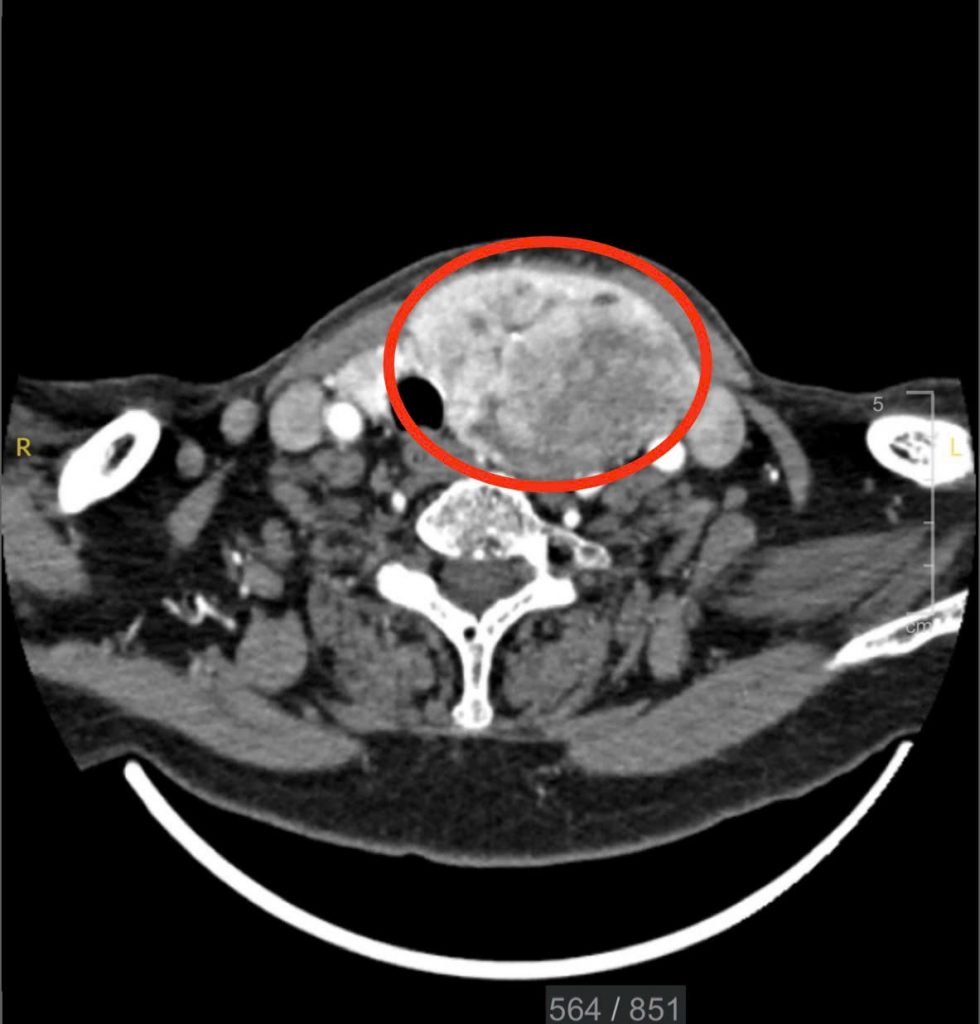

Tại phòng khám Ung Bướu, BS. CKII. Huỳnh Kiến Thành đã tư vấn và chỉ định bà chụp CT vùng cổ. Kết quả ghi nhận bà G. có bướu giáp đa nhân hai thùy khổng lồ, kích thước bướu thùy trái lên đến 9cm, bướu lộ ra ngoài.

Hình ảnh CT cho thấy khối bướu giáp

Với bướu giáp lớn, gây chèn ép thực quản khiến bà G. nuốt vướng và chèn ép dây thần kinh thanh quản khiến bà khàn giọng, nếu để lâu không mổ thì bướu sẽ tiếp tục chèn ép đường thở khiến cụ bà khó thở. Vì thế, các bác sĩ khoa Ung Bướu đã quyết định phẫu thuật bóc lấy bướu giáp, loại bỏ những biến chứng nguy hiểm cho sức của bà sau này.